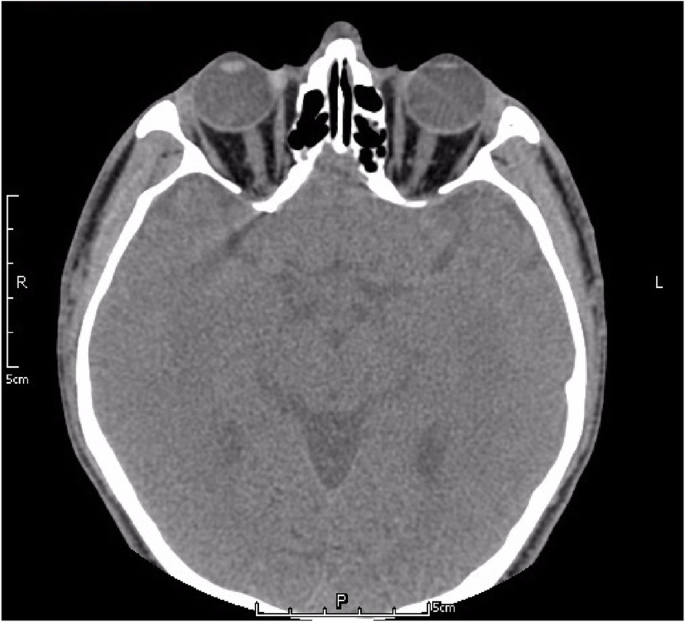

In the clinic, the visual acuity was 20/20 in his right eye (OD) and 4/20 in his left eye (OS). IOP was 13.2 mmHg OD and 34.5 mmHg OS, by Goldman applanation tonometry. Relative afferent pupillary defect (RAPD) OS was positive. Iris heterochromia and mild mydriasis OS was definite (Fig. 1). The left cornea was slightly thick and hazy with pigmented KP on the posterior surface without visible wounds or scars (Fig. 2). Gonioscopic examination uncovered a line of brownish deposits throughout the entire TM, and the anterior chamber angle was open without recession, synechiae or neovascularization (Fig. 3). Dilated fundus examination revealed retinal pigment epithelium (RPE) atrophy arranged in a leopard-spot pattern OS and obvious cup/disk asymmetry of 0.35 OD and 0.65 OS (Fig. 4). The three-mirror contact lens showed no retinal detachment or signs of IOFB. Spectral-domain optical coherence tomography (SD-OCT; RTVue-XR; Optovue, Inc., Fremont, CA) indicated central retinal thinning (Fig. 5). Using UBM (SW-3200, SUOER, China), no IOFB was detected in the anterior segment OS, including iris stroma and sclera (Fig. 6). An ultrasound B-scan (Aviso S, 10 MHz probe; Paris, France) showed moderately dense vitreous opacities with posterior vitreous detachment (PVD) (Fig. 7). The visual field, measured by Humphrey 30–2 perimetry (Zeiss Meditec, Dublin, CA, USA), showed a superior arcuate defect. An orbital X-ray and a 0.625-mm thin-sliced helical CT did not uncover any retained IOFB (Fig. 8). The amplitudes of the a and b waves were decreased on ERG (Roland Consult, Brandenburg, Germany) (Fig. 9).

Our patient presented with a six-month history of progressive blurred vision, elevation of IOP, and a change in the colour of his left eye. Slit-lamp examination revealed characteristic iris heterochromia, mild mydriasis and brownish deposits throughout the TM. No obvious corneal macula was observed. Although no solid proof of an IOFB was verified on UBM, ultrasound B-scan, or 0.625-mm thin-sliced helical CT, the possibility of siderotic glaucoma resulting from the deposition of an iron-containing IOFB could not be excluded. With the aid of ERG and histopathology (Prussian blue staining) after trabeculectomy, the patient was eventually diagnosed with siderotic glaucoma.

As iron undergoes dissolution over time and due to the limitations of ocular imaging, IOFB is not always detectable in ocular siderosis or siderotic glaucoma [12]. CT scan, ultrasound B-scan, and UBM are vital adjunct imaging tools for IOFB management [13]. CT of the orbit without contrast is the recommended approach to detect orbital foreign bodies and IOFBs. Compared with conventional CT, thin-sliced helical CT is more sensitive [14]. However, if the foreign bodies are too small or if the eye moves, the IOFB may be missed. When an IOFB cannot be visualized directly or with CT scan, a real-time, high resolution ultrasound B-scan may be helpful [15]. Nevertheless, ultrasonography can disrupt the normal anatomy of the eye and requires sophisticated machinery and skilled operators [16]. High frequency UBM (50 MHz) is a valuable technique for detecting small and anteriorly located foreign bodies in the anterior chamber and iris stroma, around the ciliary body and ciliary processes, and within the retrolental space. In this case, 0.625-mm thin-sliced helical CT, high resolution ultrasound B-scan, and UBM were used, but no foreign body was observed. Thus, we postulated that IOFB dissolution may be one of the possible reasons for our inability to detect it radiologically.